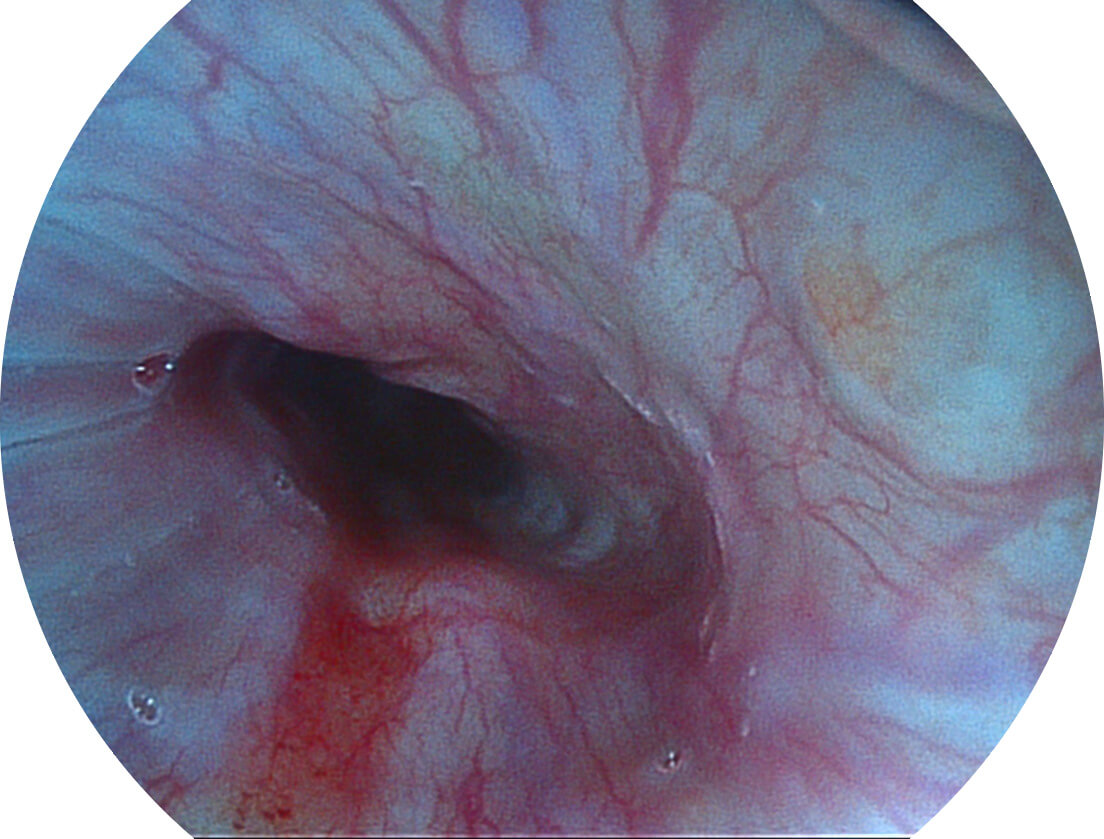

Versatile Intelligent Staining Technology, VIST

强调浅层黏膜结构的同时,保证照明亮度和提升浅层微血管与中层血管颜色对比度,病变边界更清晰。

白光图像

VIST图像